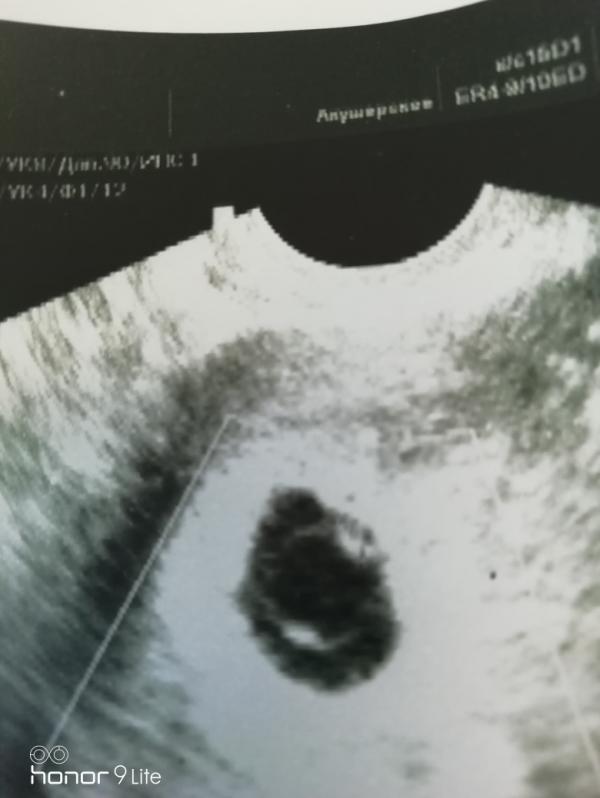

Итак у нас сегодня было второе УЗИ 🙏🙏🙏

Мы растём, сердечко послушали. Так что все хорошо. Расти наша бусинка быстрее. Мы тебя очень ждём 🙏🙏🙏